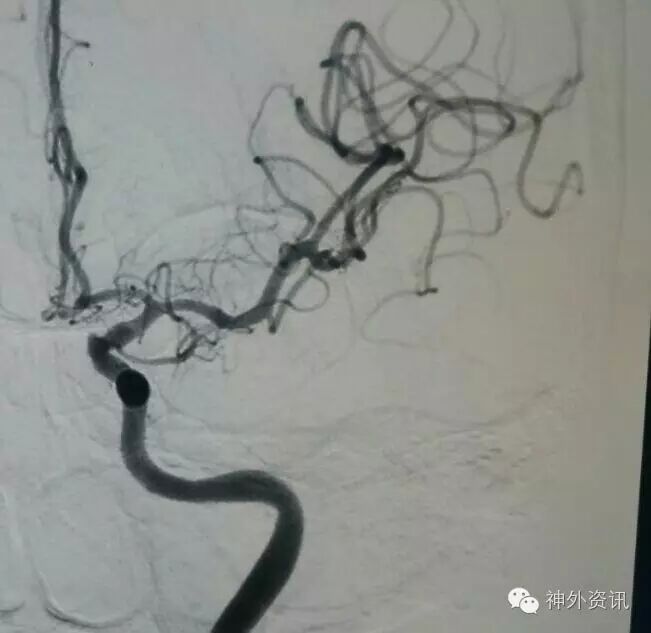

L-ICA正位

L-ICA侧位:可见床突上段前壁一突起,结合cT出血提示BBA!

R一ICA正位未见异常!

R-ICA侧位正常

3D示BBA基底宽约3.5mm,局部突起高约1.5mm。

病人前交通开放良好,如BBA段颈A壁破损范围广,必要时可考虑ICA孤立!